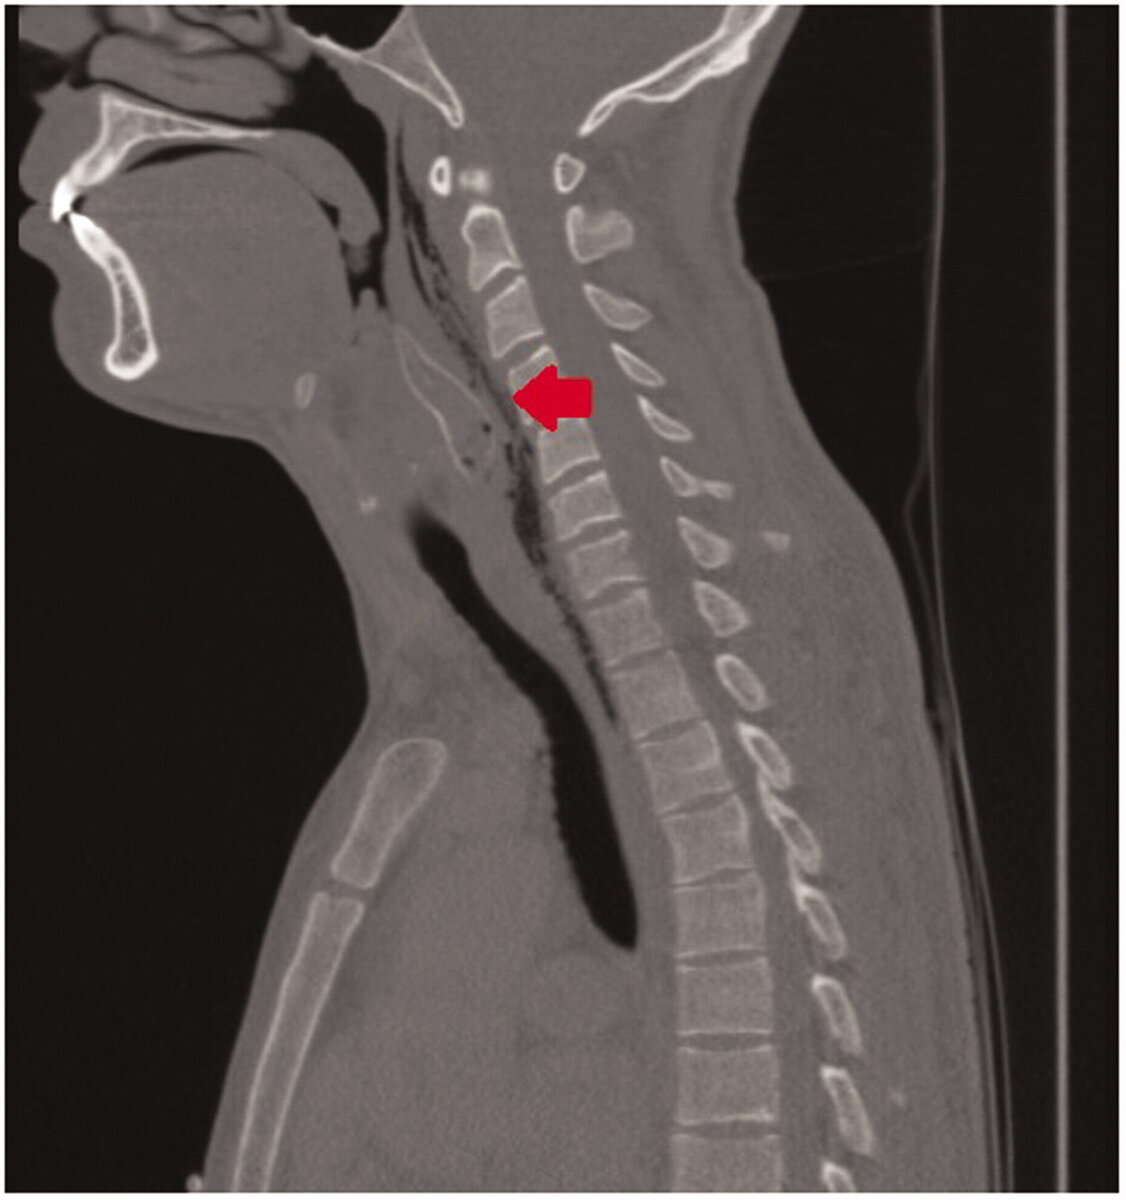

Когда мужчина наконец добрался до отделения неотложной помощи, врачи осмотрели его горло с помощью инструмента, называемого ларингоскопом, и обнаружили, что они описали как «рыбоподобную структуру», согласно отчету.

Изображение показывает, как этот сом выглядел в горле человека до удаления. Предоставлено: Бенуа и др.